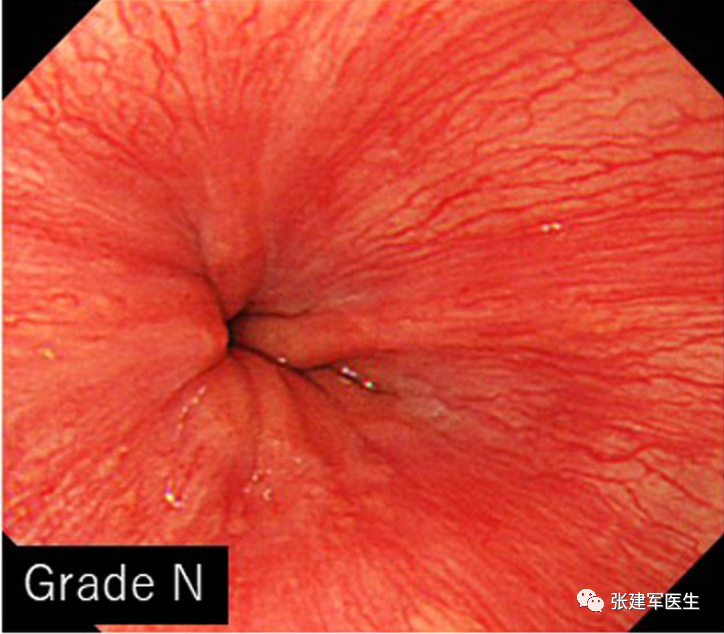

胃十二指肠镜检查

能直观评估食管、胃以及十二指肠粘膜状态,诊断糜烂性食管炎及巴雷特食管(Barrett's esophagus),明确食管裂孔疝的大小及类型,确定食管裂孔疝有无扭转。